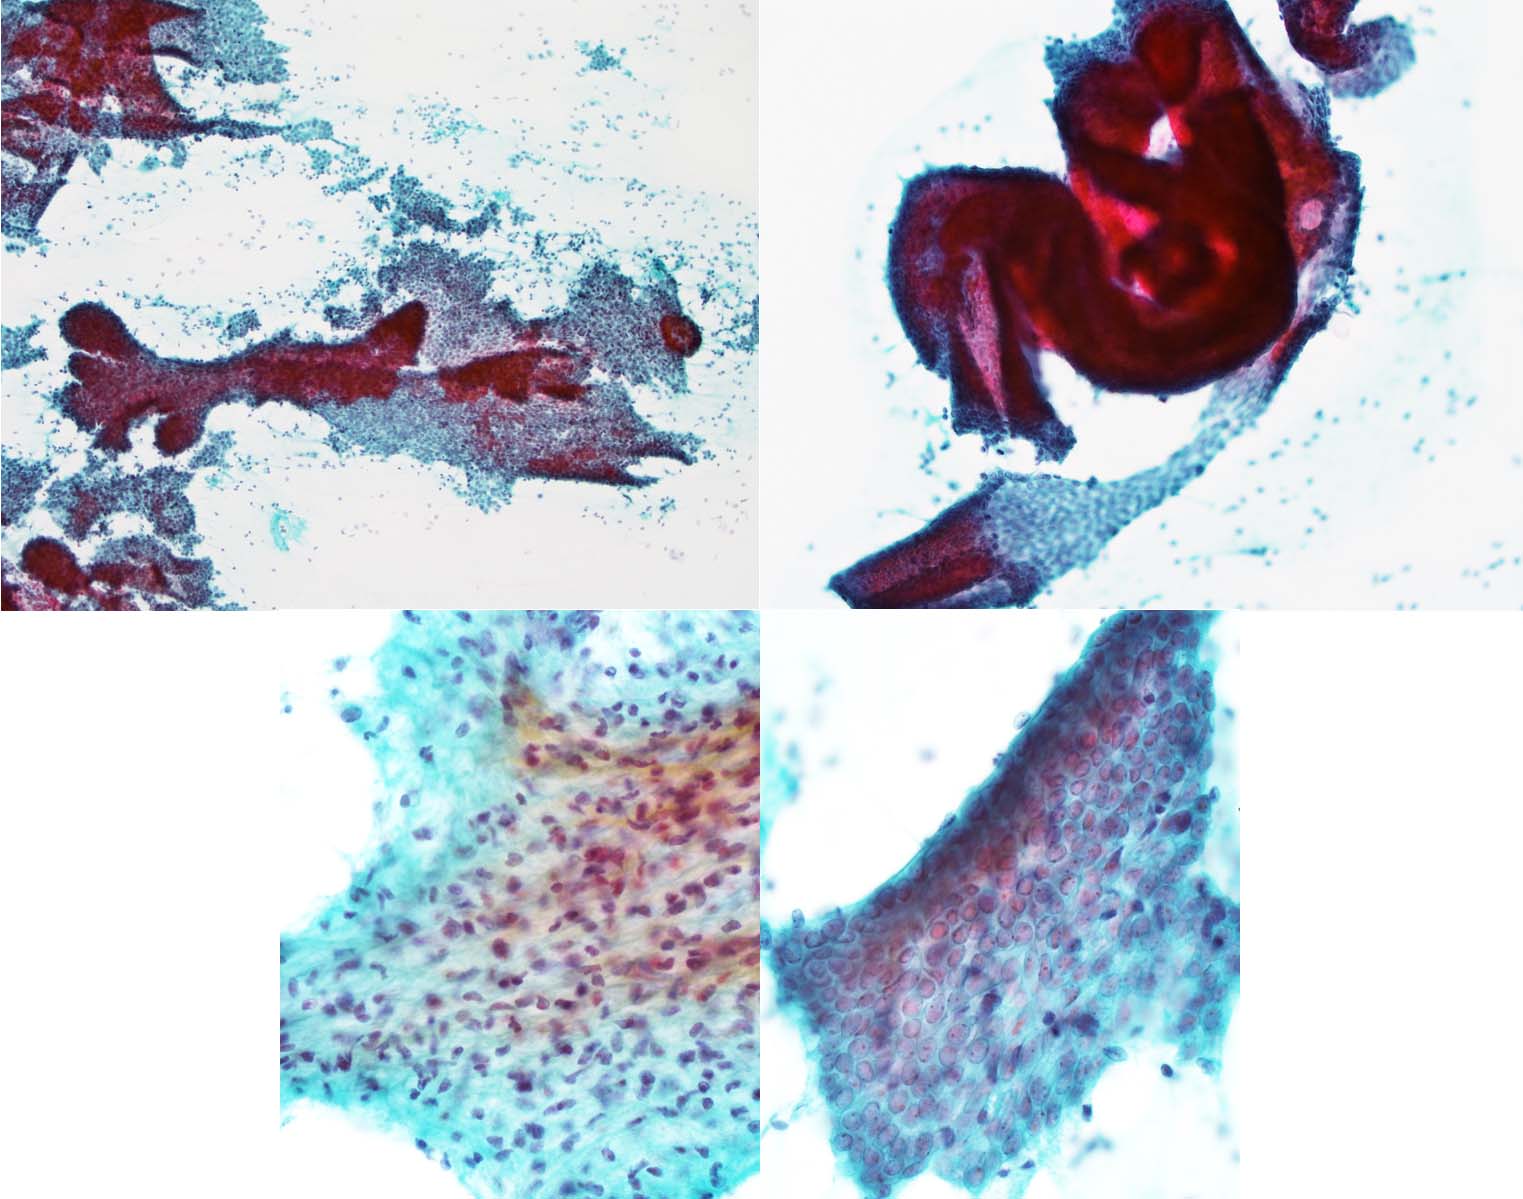

- 乳管内に生ずる良性腫瘍で、血管結合組織の軸を有する上皮細胞と筋上皮細胞の増殖である。乳輪付近の太い乳管に発生する中心性乳頭腫と小葉に発生する末梢性乳頭腫に分けられる。なお「乳頭腫症(papillomatosis)」という用語は上皮過形成を意味する場合と多発性乳頭腫を意味する場合がある。曖昧な「乳頭腫症」というコトバは使用を避けるべきである。